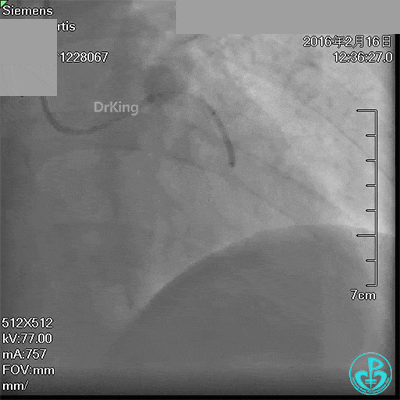

急诊术中导丝在锁骨下通过困难,曾在局部推注造影剂造影,回顾造影结果发现局部小血管破裂造影剂渗漏。